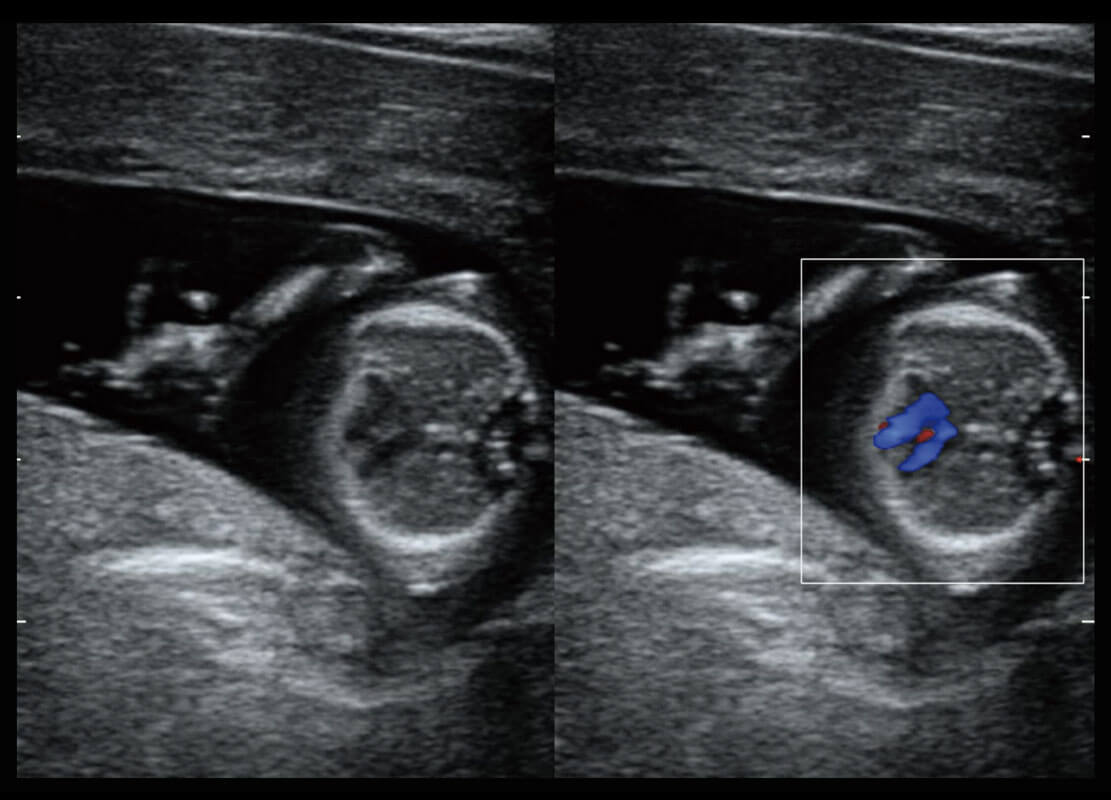

• 四腔切面

• 四腔心血流

P60搭载一系列胎儿心脏成像技术,实现精细的胎儿心脏评估。